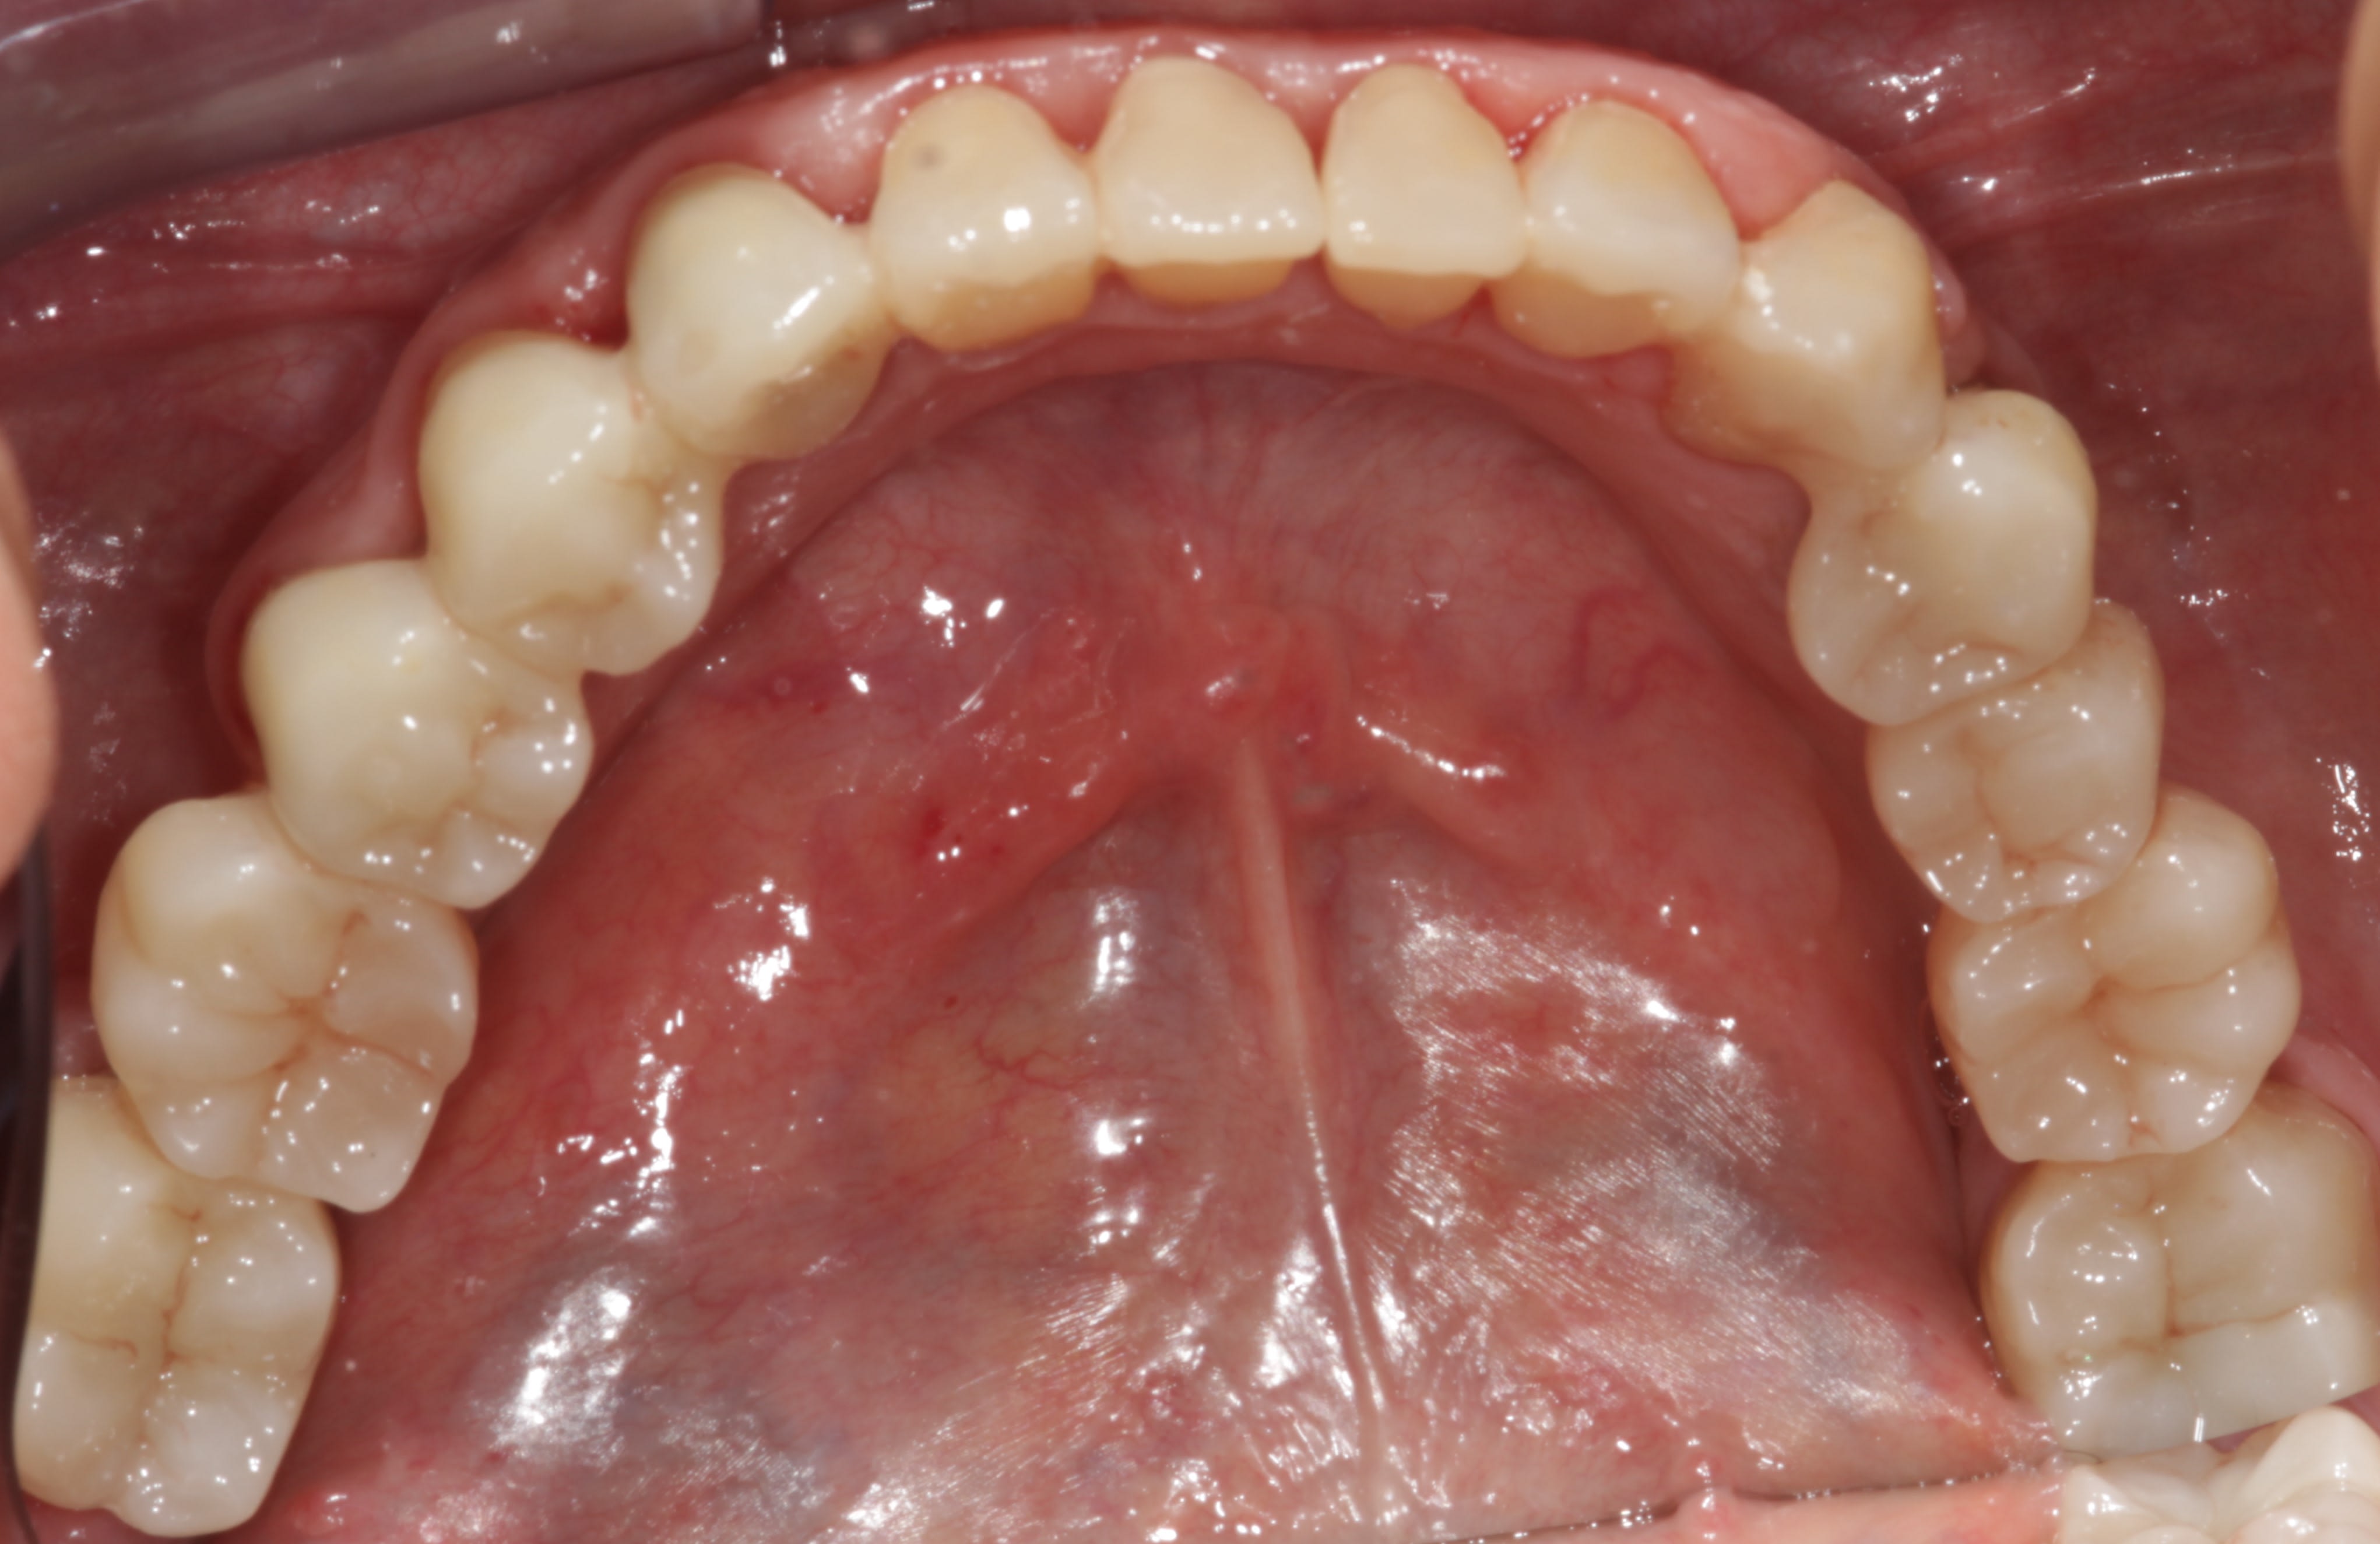

Essais ! Tiens regarde ce cas , temps de prise d’empreinte hyper rapide , pose de 15 couronnes ( full anatomique ) en zr qui au passage à tellement progressé qu’on dirait des emax (full) egalement rapide et sans retouche occ !!

Pour que ça pisse pas trop. Loupes fois 5 pour éviter de toucher la gencive. Quand tu peux pas faire autrement expasyl si ca résiste laser. Ici en distal de 44.

En sous gingival c'est franchement pas un problème.

Tu l'as déglinguée avec quoi, laser bistouri électrique, fraise ?